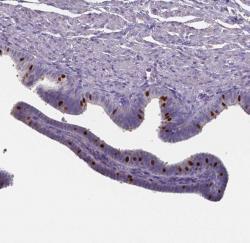

Image of the month - Ciliated cells in the fallopian tubes

A recent addition to the single cell type section are the ciliated cells in the fallopian tubes. Ciliated cells in the fallopian tube play an important role in the female reproductive system, facilitating successful fertilization and transport of gametes. This time, we focus on the elevated expression of the genes forkhead box J1 (FOXJ1) and dynein axonemal intermediate chain 2 (DNAI2)...Read more